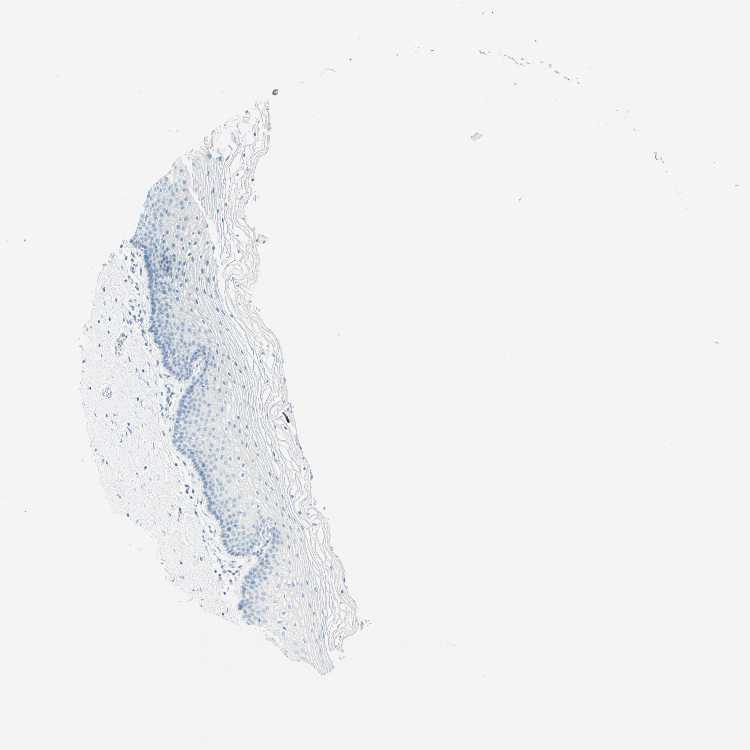

TMEM132D